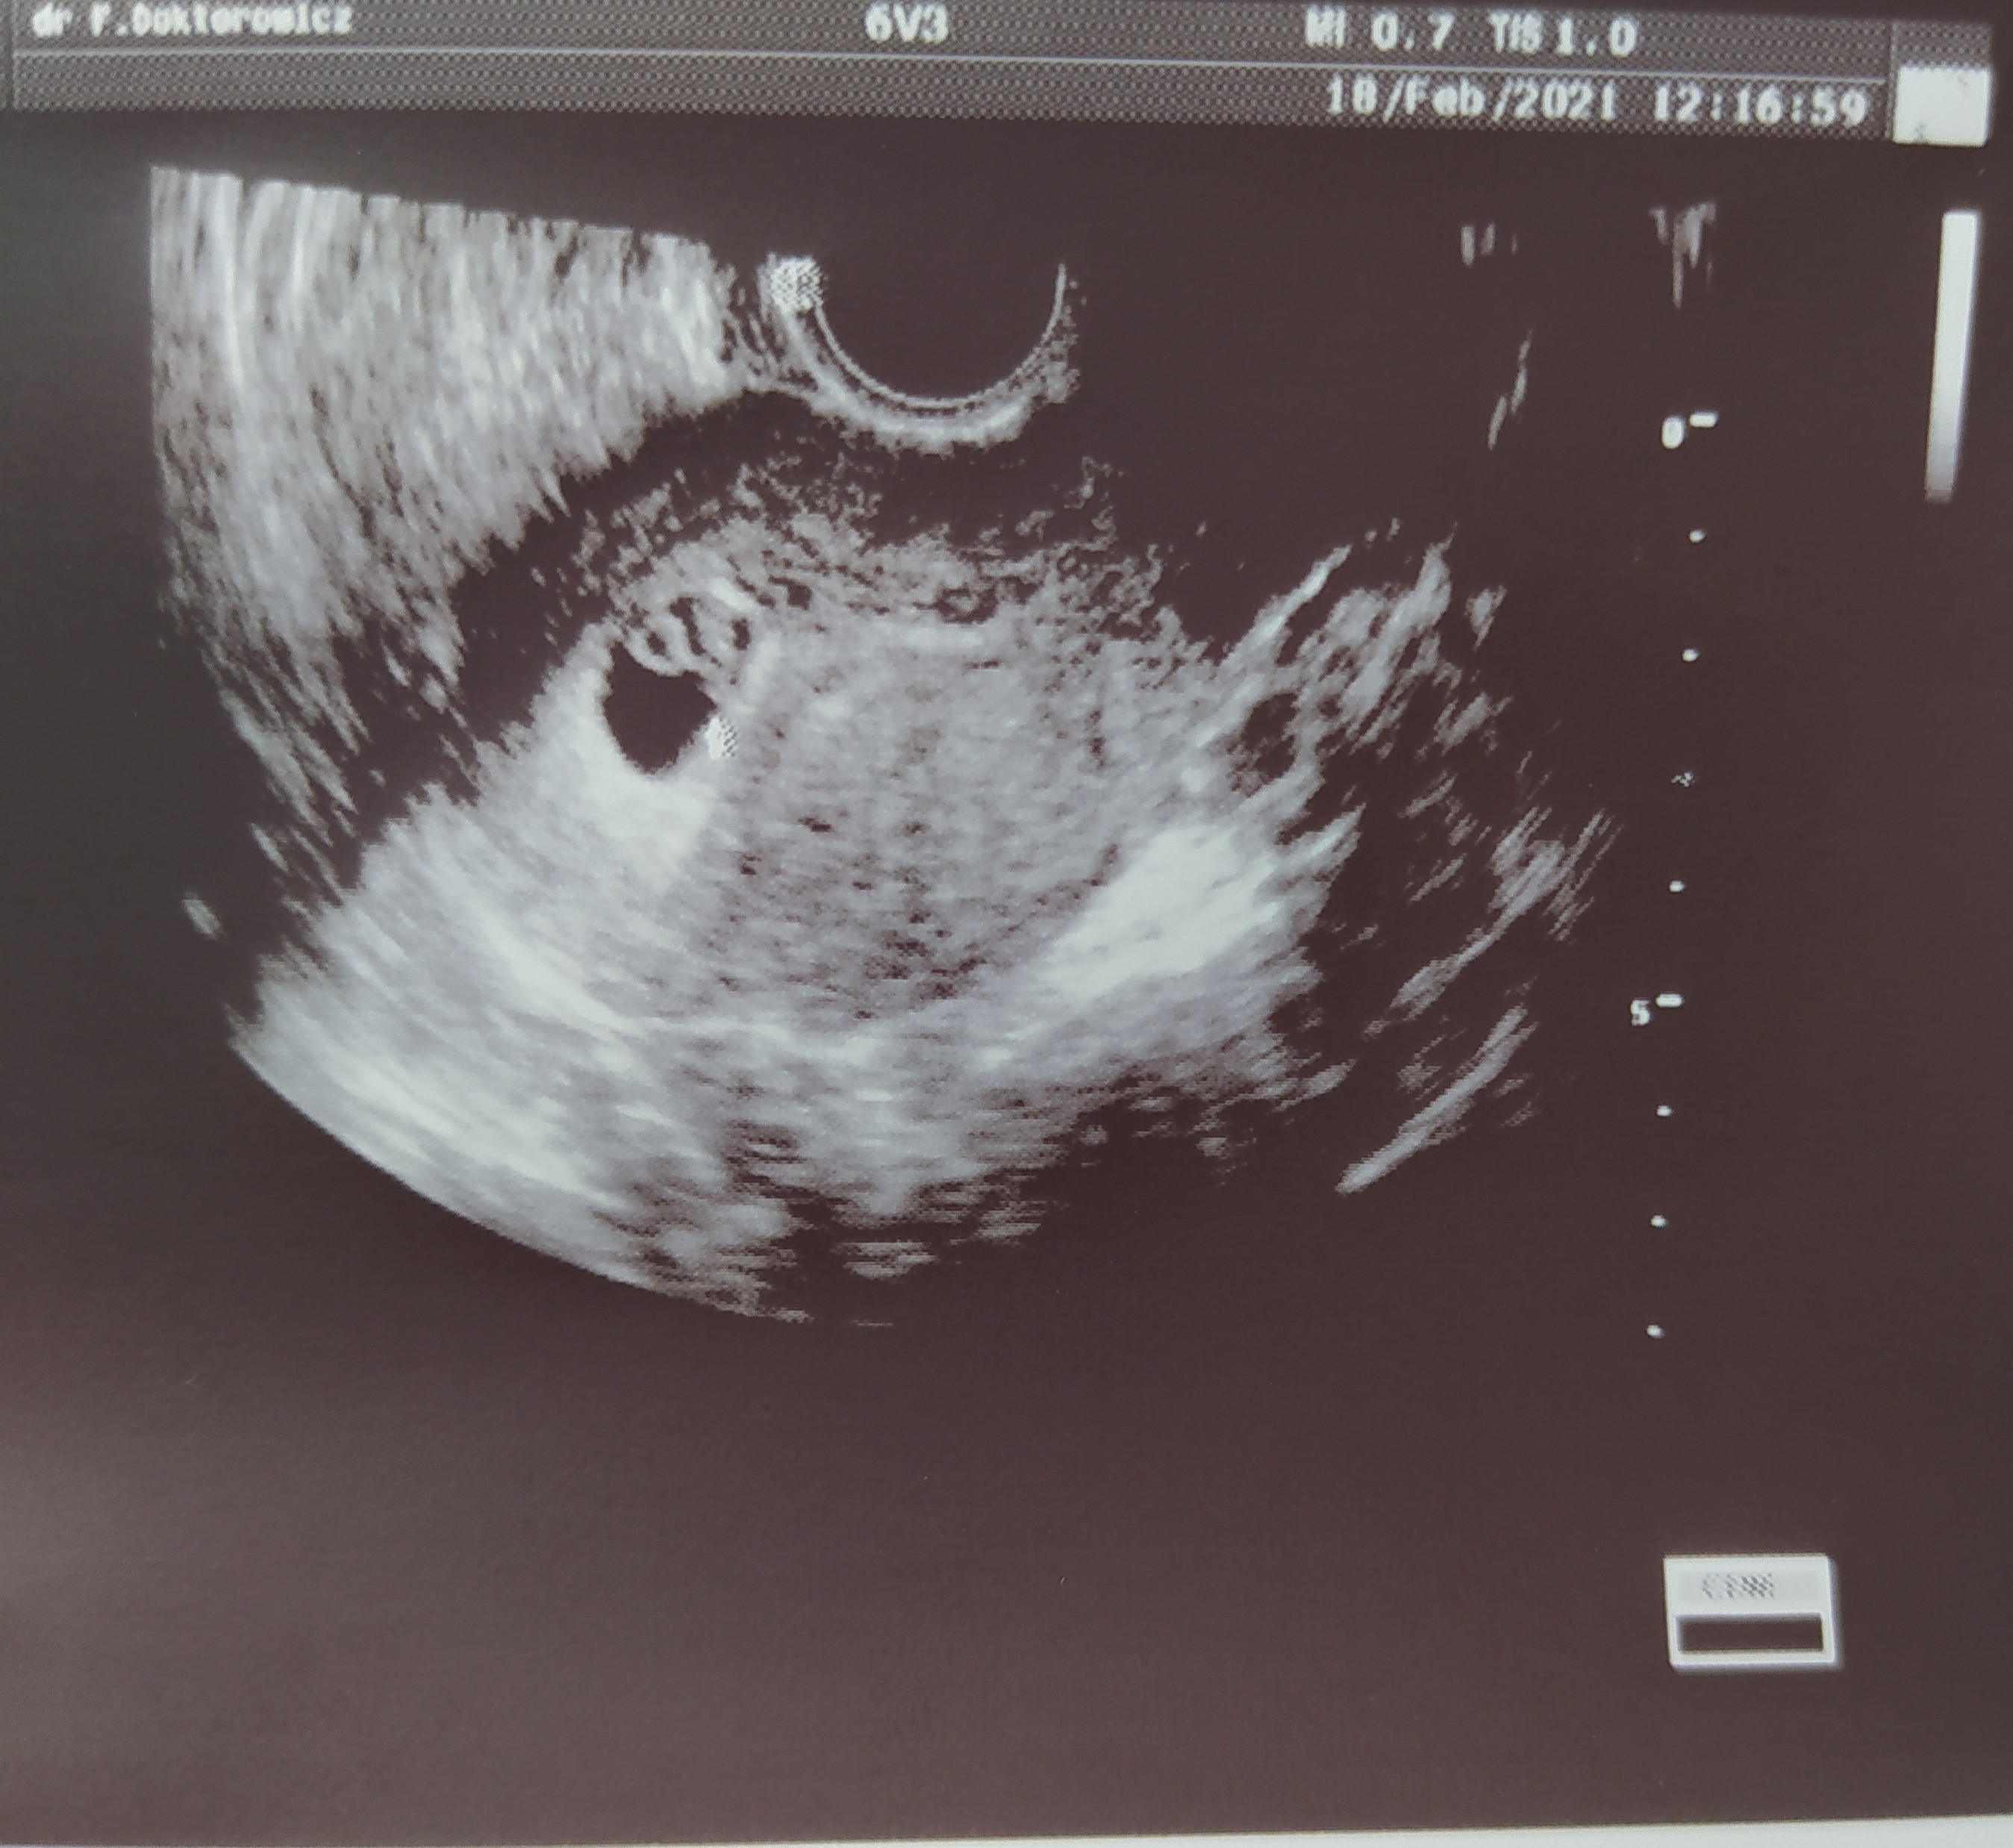

Zastanawiam się w którym tygodniu iść, ponieważ w pierwszej ciąży w 7 tyg miałam już takie usg. I nie wiem czy jakbym poszła teraz w 6 tyg czy też by było tak widoczne

Załączniki

• IMG_20210218_141249.jpg

IMG_20210218_141249.jpg

165,6 KB · Wyświetleń: 87